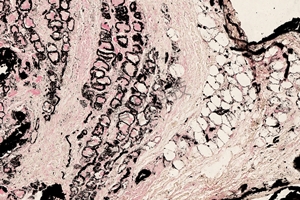

VonKossa钙化染色

染色利用金属离子置换反应检测组织中钙盐沉积,由硝酸银溶液中的银离子置换组织中沉积的钙离子。